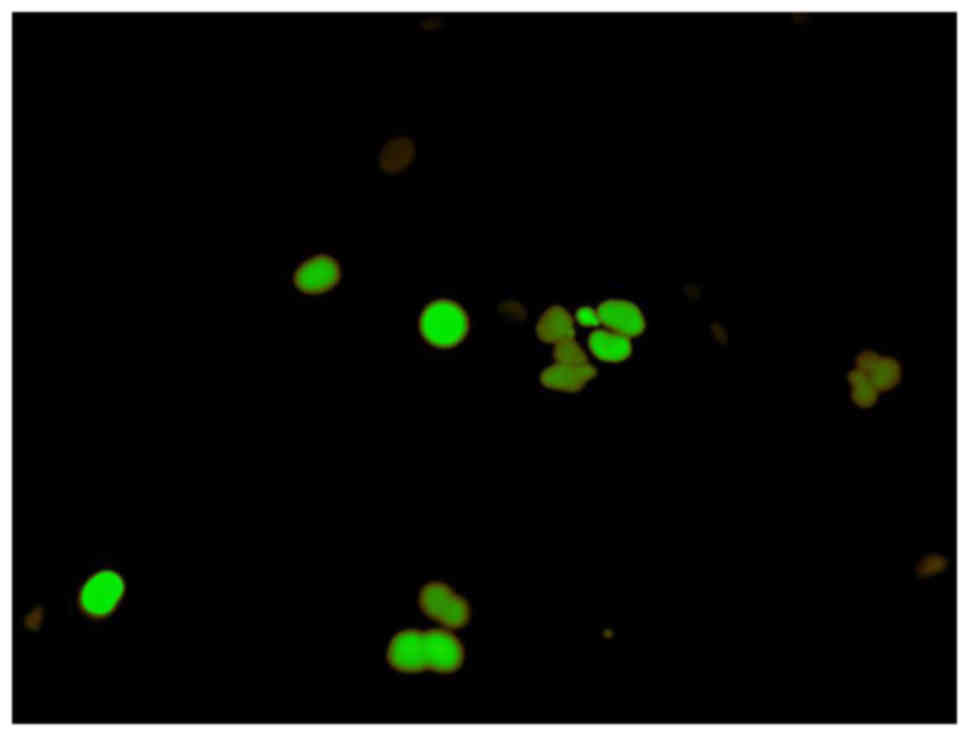

Analysis of cell cycle arrest

To determine the stage of the cell cycle at which the SAS cells were arrested, they were treated with α-mangostin (20 µM) + rhTRAIL (100 ng/ml) for 24 h, and then examined using Fluorescent Ubiquitination-based Cell Cycle Indicator (FUCCI). FUCCI is a fluorescent cell cycle indicator that harnesses the ubiquitination oscillators that control cell cycle transitions. The original FUCCI probe was generated by fusing mAG (monomeric Azami-Green) and mKO2 (monomeric Kusabira-Orange 2) to the ubiquitination domains of human Geminin and Cdt1, respectively. These two chimeric proteins, mAG-hGem and mKO2-hCdt1, accumulate reciprocally in the nucleus of transfected cells during the cell cycle, labeling the nuclei of the S/G2/M-phase cells green and those in the G1 phase red. An mAG-hGem and an mKO2-hCdt1 expression vector were purchased from Medical and Biological Laboratories (Nagoya, Japan). To establish SAS cells transiently expressing mAG or mKO2, the parent cells were transfected with each plasmid using Lipofectamine (Invitrogen, Carlsbad, CA, USA) for 24 h. The transfected cells were then treated with α-mangostin (20 µM) + rhTRAIL (100 ng/ml) or PBS as a control for 24 h and observed by fluorescence microscopy.

To determine whether caspase-dependent apoptotic activity could be modulated by combined treatment with α-mangostin and rhTRAIL, the SAS cells were treated with α-mangostin (20 µM) and rhTRAIL (100 ng/ml), or left untreated as a control, for 24 h. Subsequently, we examined the cleavage of procaspase to active caspase-8, −9 and −3/7, markers of apoptotic activity, in SAS cells. The levels of caspase-9 and −3/7 were increased in response to α-mangostin and rhTRAIL, which revealed more than a two-fold increase of activity at 24 h, in the SAS cells relative to the control (Fig. 4). This finding indicated that the combined treatment with α-mangostin and rhTRAIL led to apoptosis of the SAS cells via activation of caspase-3/7 and −9. We also used FUCCI to determine which stage of the cell cycle arrest occurred. This revealed that treatment with both α-mangostin and TRAIL induced S/G2/M-phase arrest and not G1-phase arrest, in SAS cells (Fig. 5).

Figure 5.

Cell cycle analysis. Treatment with both α-mangostin and TRAIL induced S/G2/M-phase arrest and not G1-phase arrest, in SAS cells.